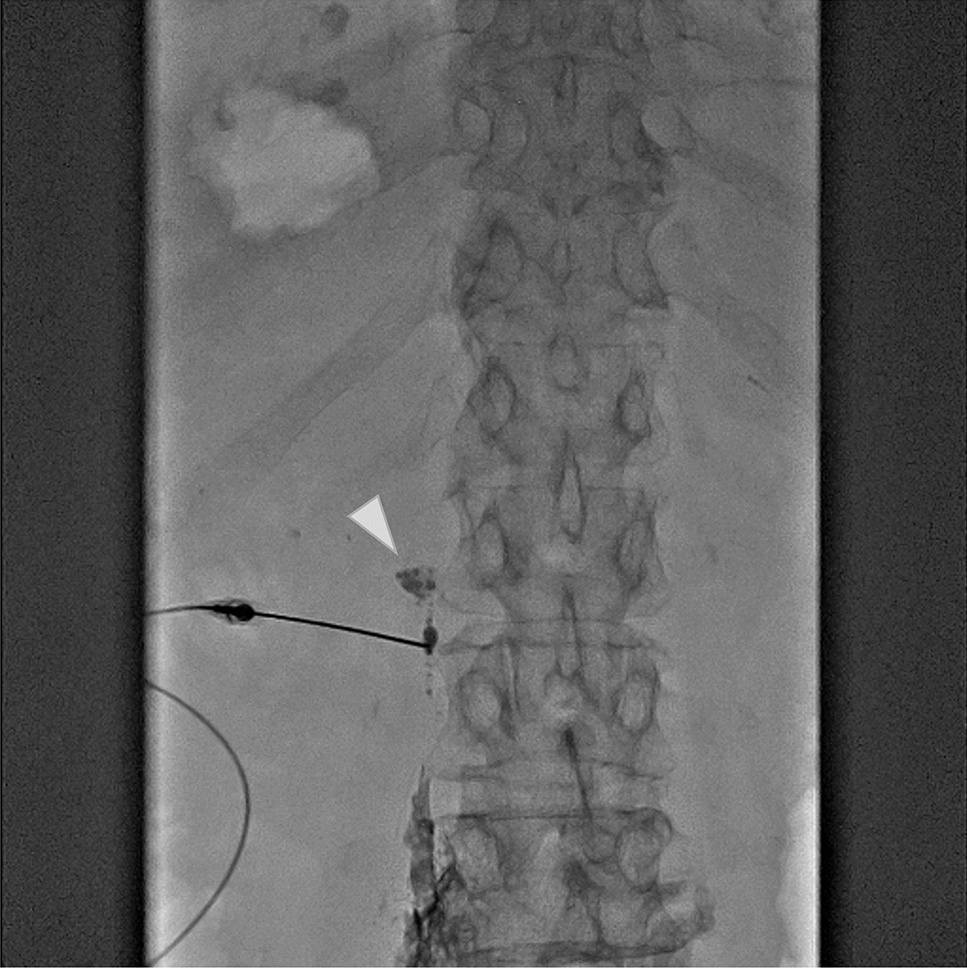

Stereotactic body radiation therapy (SBRT) is the standard treatment for patients who are medically inoperable or who refuse surgery with stage I non-small cell lung cancer (NSCLC). While acute lymphopenia following SBRT is documented, the long-term effects on the immune system and infectious disease remain unclear. In this report, we present two cases of chronic progressive pulmonary aspergillosis (CPPA) occurring within the irradiated field following SBRT for inoperable stage I NSCLC. Case 1 was a man in his 70 s with a history of smoking and a previous pulmonary resection and SBRT for metachronous primary lung cancer. He received SBRT for T1aN0M0 NSCLC in the right lower lobe as his third primary lung cancer. After 20 months, the patient developed a cough and sputum, and a computed tomography (CT) scan revealed a cavity shadow in the irradiated field, which led to the diagnosis of CPPA. Intravenous voriconazole was immediately started, and after 3 week’s administration, the symptoms improved, and the cavity disappeared. After 34 months, the patient died with no recurrence of CPPA and lung cancer. Case 2 was a man in his 80 s with a history of smoking and previous pulmonary resection for lung cancer. He received SBRT for T1cN0M0 NSCLC in the right lower lobe as his second primary lung cancer. After 19 months, the patient developed a fever, and a CT scan revealed a cavity shadow in the irradiated field, which led to the diagnosis of CPPA. Oral itraconazole was administered, followed by diarrhea and anorexia. After 22 days, the patient died. During the follow-up period, there was no recurrence of lung cancer. Risk factors for CPPA include a history of smoking and lung resection, common among candidates for pulmonary SBRT. When a cavity shadow develops following SBRT, differentiating consolidation as radiation pneumonitis, local recurrence, or infection can be challenging. When a cavity is identified on a follow-up CT scan after SBRT, it is crucial to include CPPA in the differential diagnosis.